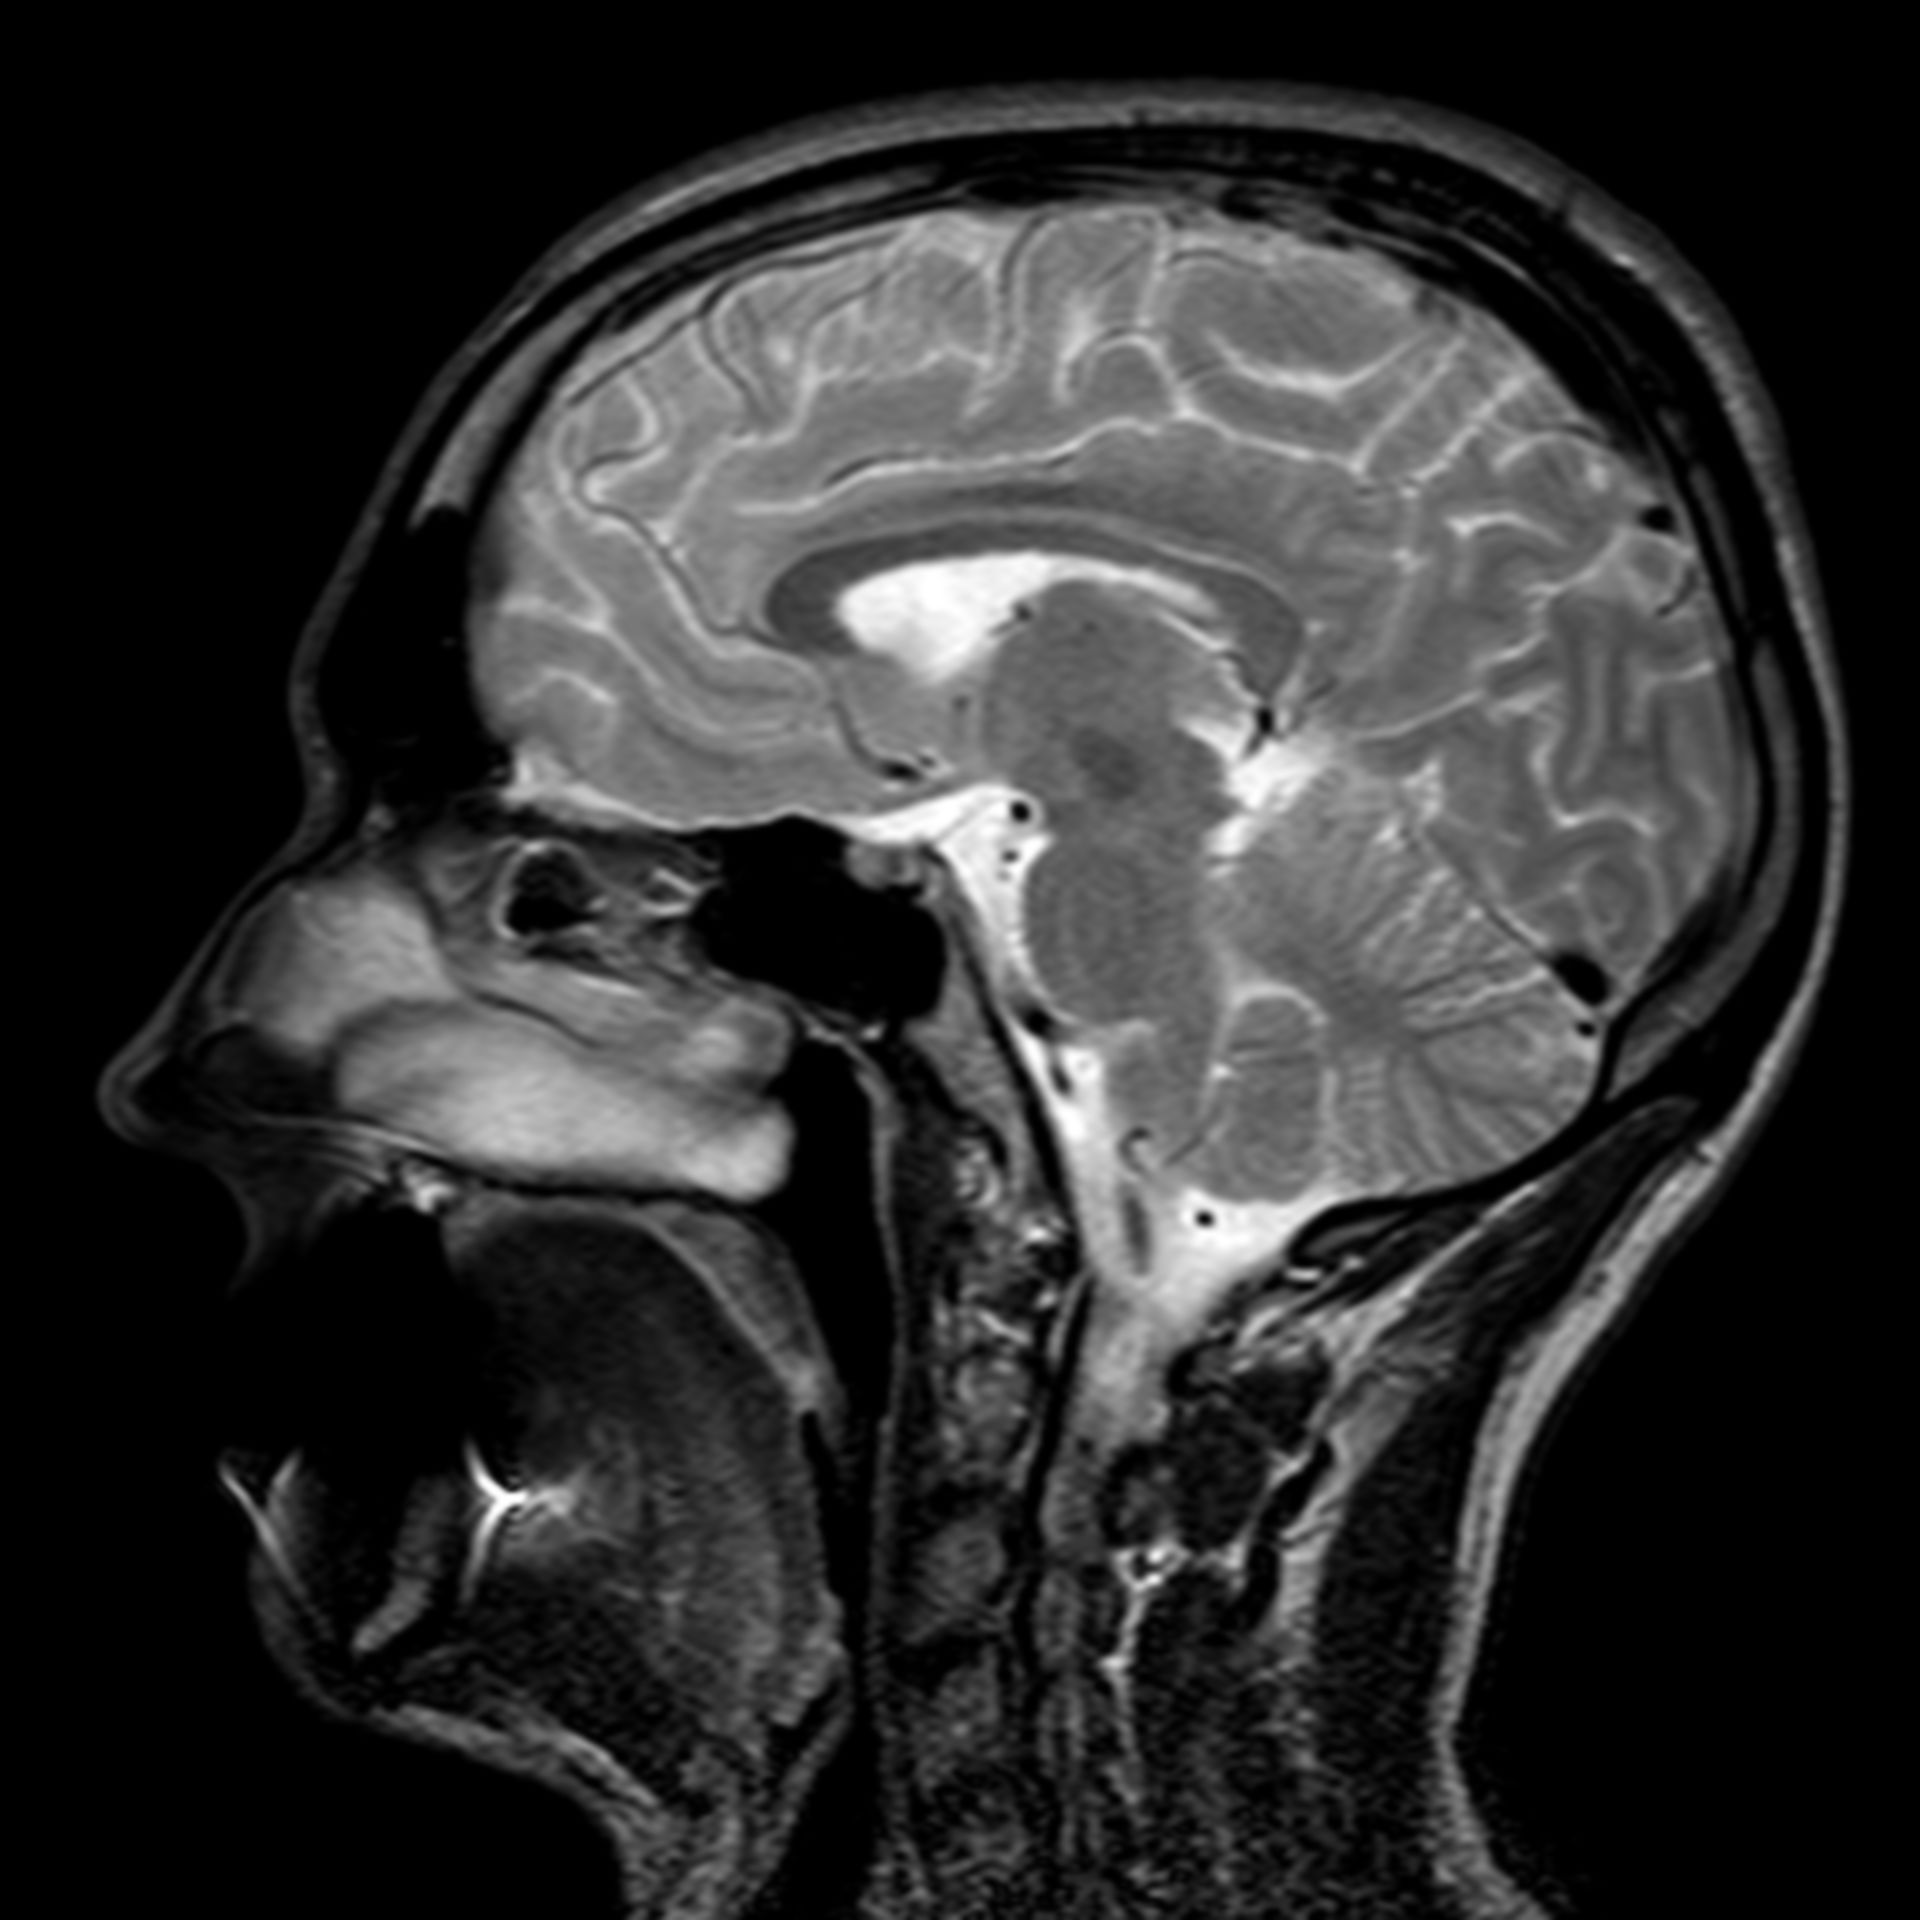

MRT Bild vom Kopf: Was ist das am rechten Ohr? (Nasennebenhöhlen) MRT Schädel, was ist das? (MRT Befund, Kontrastmittel)

MRT Bild vom Kopf: Was ist das am rechten Ohr? (Nasennebenhöhlen) MRT Bilder vom 18. Februar 2002

MRT Kopf. Kleine Aufklärung? (Gesundheit, Medizin, Krankheit) Retinoblastom (MRT/T2) – DocCheck

(16/34) MRT Schädel in Sagittalebene, T₂‐gewichtet – DocCheck MRT Bilder-Hubbel-??? Hilfe (Kopf)